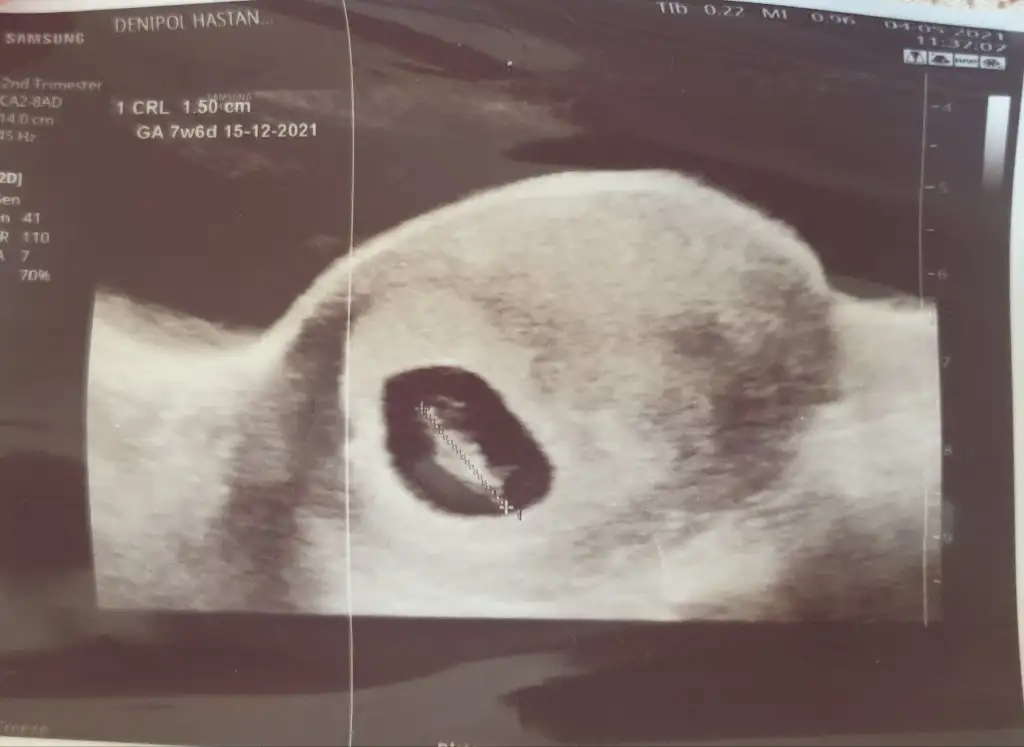

Bana da bakarmisiniz lutfen 🙏🙏

Benim 6+4 de bi sag da bi solda gorundu..

7+6 goruntude ortada gorundu... hepsi de karından 🙏